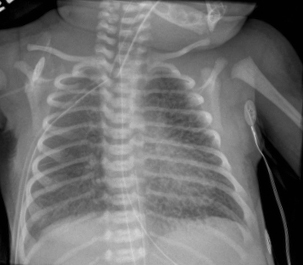

신생아 호흡곤란 증후군은 미국에서 모든 출생의 약 1%에서 출생 후 6시간 이내에 가장 흔하게 발생한다.[18] 주요 위험 요인은 미숙아이며, 750g 미만의 영아에서 발생 가능성은 최대 71%까지 증가한다.[19] 다른 위험 요인으로는 당뇨병 산모의 영아(IDM), 분만 방법, 태아 질식, 유전학, 막의 장기 파열(PROM), 임신 중독증, 융모 양막염, 남성 성별이 있다. 호흡곤란 증후군의 널리 받아들여지는 병태생리는 불충분한 폐활량소 생성과 미숙한 폐 및 혈관 발달로 인해 발생한다는 것이다. 폐활량소 부족으로 인해 폐가 무기폐가 되어 환기/관류 불일치, 감소된 폐순응도 및 증가된 기도 저항이 발생한다. 이로 인해 저산소증과 호흡성 산증이 발생하여 폐 고혈압으로 이어질 수 있다. X선 사진에서 ground glass appearance(모래알 유리 모양)을 보인다. 증상으로는 빈호흡, 비강 확장, 역설적 흉부 운동, 그렁거림 및 늑골 하부 함몰이 포함될 수 있다.[18]